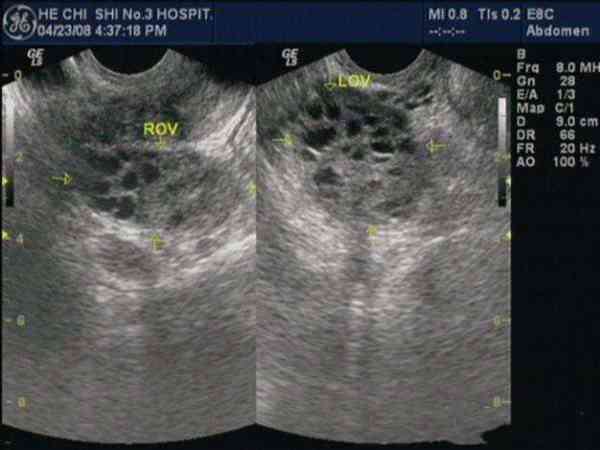

703 浏览 11-15多囊卵巢综合症是临床上常见的一种妇科疾病,很多育龄女性在医院检查后发现患有该疾病...

52 浏览 11-15多囊卵巢是可以怀孕的,患病的女性通常会有多个卵子同时发育,而导致没有一个优势卵泡...